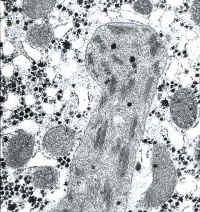

li-8-4-16.jpg (75249 bytes)

Fig. 8-4-16:

Giant Mitochondria